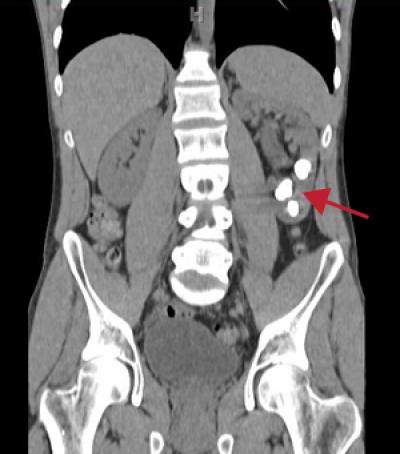

Most kidney stones form when the urine becomes too concentrated, allowing minerals like calcium to crystallize and stick together. Diet plays a role in the condition — not drinking enough water or eating too much salt (which binds to calcium) also increases the risk of stones.

Without a way back to the bloodstream, excess calcium goes into the urine. Too much calcium in the urine can lead to stones in the kidneys or bladder. Intense pain develops when a large stone gets stuck in the bladder, ureter or urethra and blocks the flow of urine.